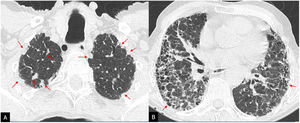

Although classically, it has been considered that fibrosis in FHP predominates in the upper lung fields, being a distinctive feature of IPF,29 FHP-associated fibrosis has been found to affect the lower lung fields in more than 50% of cases. Honeycombing may be present and extensive in severe forms and indistinguishable from that of IPF.30 The UIP pattern has been included in the 2020 ATS/JRS/ALAT multidisciplinary guidelines for the diagnosis of HP in the category of HRCT compatible with FHP.31 Additional findings that should lead to suspicion of FHP in a UIP pattern are the presence of small airway involvement in the form of poorly-defined centrilobular nodules or the mosaic attenuation pattern of lobular morphology or the three-density pattern, highly specific for NHF, or air trapping on expiration, especially if present in areas without fibrosis31,32 (Fig. 8).

Figure 8.

Patient with fibrotic hypersensitivity pneumonitis diagnosed by lung biopsy. A–D) High-resolution computed tomography axial plane images revealing signs of patchy fibrosis with traction bronchiolectasis and small honeycomb cysts (arrows) and a mosaic attenuation pattern with areas of hypoattenuation (asterisks) indicative of air trapping.